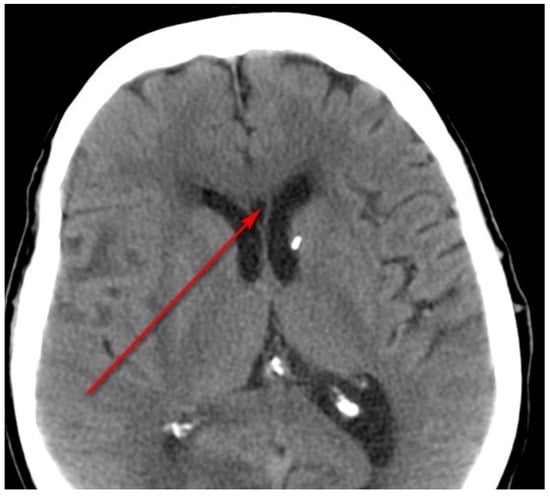

2.6. Neuroimaging Scan Evaluation for the Presence of the CSP

- Kasai, K.; McCarley, R.W.; Salisbury, D.F.; Onitsuka, T.; Demeo, S.; Yurgelun-Todd, D.; Kikinis, R.; Jolesz, F.A.; Shenton, M.E. Cavum septi pellucidi in first-episode schizophrenia and first-episode affective psychosis: An MRI study. Schizophr. Res. 2004, 71, 65–76. [Google Scholar] [CrossRef]

- Winter, T.C.; Kennedy, A.M.; Byrne, J.; Woodward, P.J. The cavum septi pellucidi: Why is it important? J. Ultrasound Med. 2010, 29, 427–444. [Google Scholar] [CrossRef]

- Bodensteiner, B.; Schaefer, G.B. Wide cavum septum pellucidum: A marker of disturbed brain development. Pediatr. Neurol. 1990, 6, 391–394. [Google Scholar] [CrossRef]